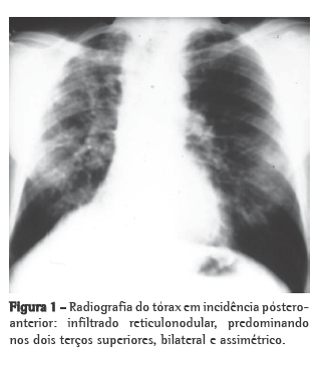

11- Paracoccidioides brasiliensis

Radiologia